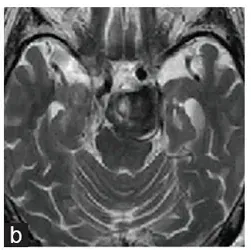

诊断4个月后的血管造影显示动脉瘤直径为12毫米,起源于后交通动脉。

2年3个月后,王叔的复查MRI结果让所有人揪心:动脉瘤直径已经涨到30mm,里面还形成了血栓,而这些血栓正死死压迫着脑干和丘脑——这两个部位是大脑的“指挥中心”,管着身体运动、意识和神经功能。

诊断2年3个月后磁共振成像显示动脉瘤内有血栓,直径达30mm,压迫脑干。

图C:在磁共振成像和三维ct血管造影上,病灶直径扩大到35mm。

图D:6个月后动脉瘤从后交通动脉向上扩张。右侧大脑后动脉未见。